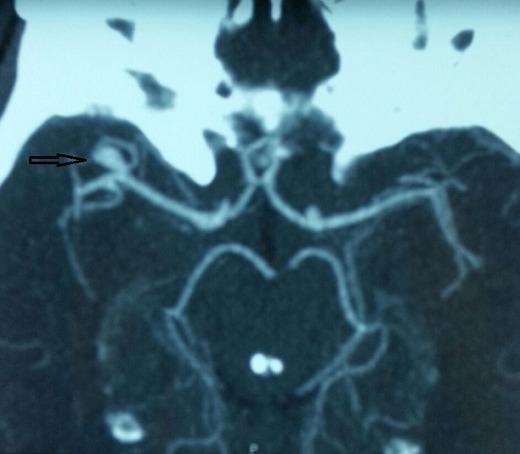

[大脑外侧裂和肠系膜动脉动脉瘤揭示感染性心内膜炎]

[Sylvian and mesenteric arteries aneurysm revealing infective endocarditis].

Infective endocarditis is an emergency condition usually diagnosed in the context of an infectious syndrome associated with heart murmur. It can lead to life-threatening complications. We report the case of a patient with endocarditis presenting as neuro-abdominal manifestations associated with sylvian and mesenteric arteries mycotic aneurysm. Evolution was favorable under medical-surgical treatment.

摘要

感染性心内膜炎是一种通常在伴有心脏杂音的感染综合征背景下诊断出的急症。它可导致危及生命的并发症。我们报告一例以与大脑外侧裂和肠系膜动脉霉菌性动脉瘤相关的神经腹部表现为特征的心内膜炎患者。在内科 - 外科治疗下病情转归良好。